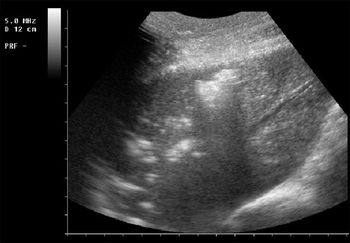

Cats with respiratory distress represent a significant diagnostic and therapeutic challenge to the small animal veterinarian.

Lower respiratory tract disease produces typical clinical signs in cats, including chronic cough and wheeze as well as dyspnea that may have a sudden onset.

The pleural space is defined as the area between the lungs and the chest wall.